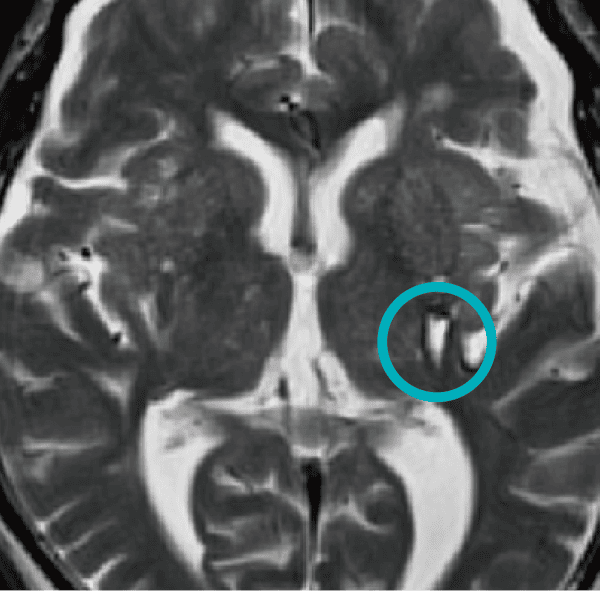

海綿状血管奇形

海綿状血管奇形は、以前海綿状血管腫と呼ばれた腫瘤状の血管病変で、出血を繰り返して徐々に大きくなり、時に症状(頭痛・けいれん・脳卒中)を呈することがあります。変化を見るために定期検診をおすすめします。症状が出現ないし悪化した際は、直ちに医療機関を受診してください。